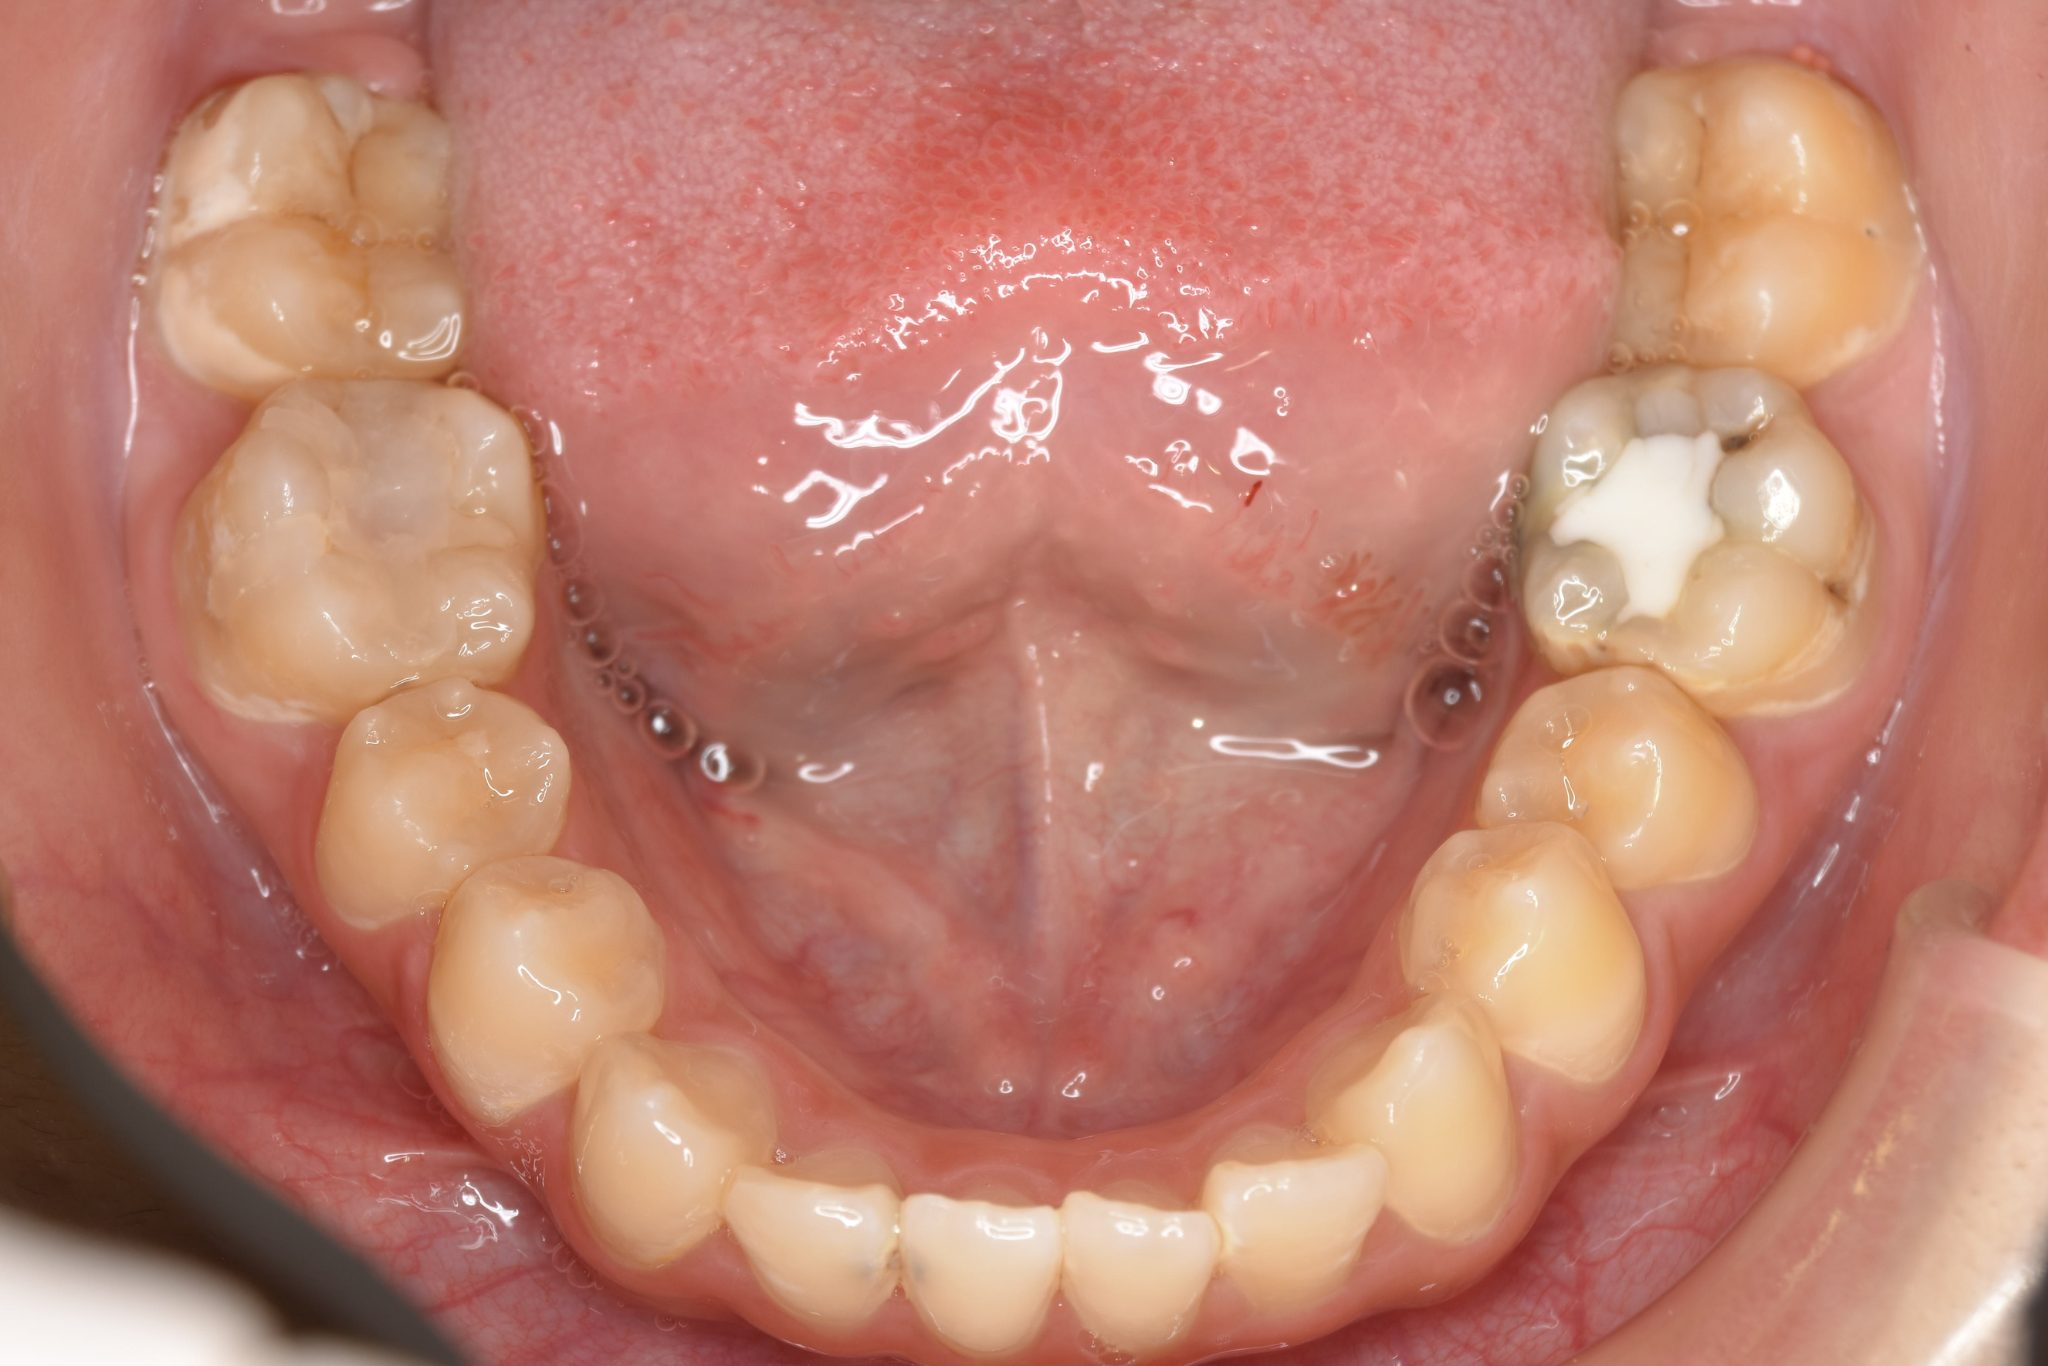

ビフォー

主訴 歯並び|かみ合わせ

施術内容 MSEと下顎リンガルアーチを用いて上下顎骨を拡大した。

その後マルチブラケット装置を用いて非抜歯で歯牙を配列し良好な咬合を獲得した。

吸指癖と鼻閉症状は改善した。

治癒期間 2年2か月間